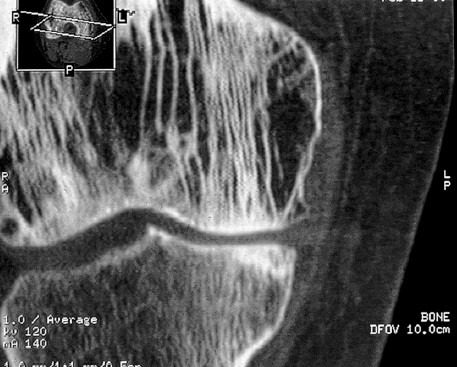

c. IRM et scanner (figure 1.10)

Ils n’ont pas d’intérêt sauf dans les rares cas de diagnostic difficile et dans l’exploration de certaines complications de la maladie (compression radiculaire ou médullaire, dégénérescence sarcomateuse).

Fig. 1.10. Maladie de Paget osseuse. Aspect scannographique. La trame osseuse de l’extrémité inférieure du fémur apparaît « grossière » caractérisée par une hypertrophie des travées osseuses